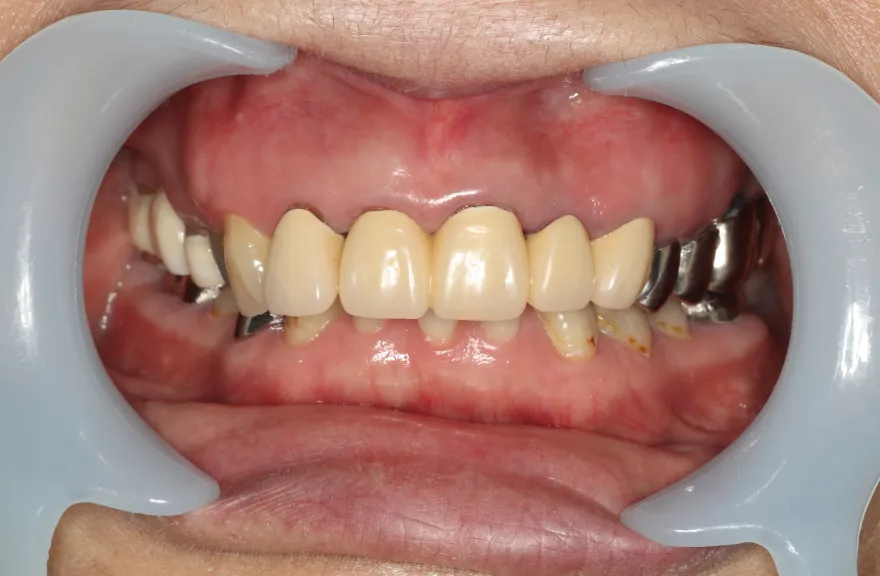

上顎は5本の歯を保険のブリッジ治療で連結してある状態でした。どの歯の状態も良くなく、今回なんとか治療を行ったとしても近いうちに再びトラブルを起こしてくることが予想されました。

下顎は9本の歯が残っており、虫歯はあるものの差し歯として使える状況でした。

しかし、患者さんとの話し合いの中で、「数年前に行った治療なのに再び全てやりかえないといけないのは単純にしんどい。もうやりかえのないようにしたい」という患者さんの強い思いが伝わってきました。

今回で完全に治療をやり切ってしまい、今後は最小限の介入で歯科と付き合えるよう、上下顎残っている歯の全ての抜歯、必要な本数のインプラント埋入、上顎は総義歯形態で対応することとしました。 - 治療のリスク